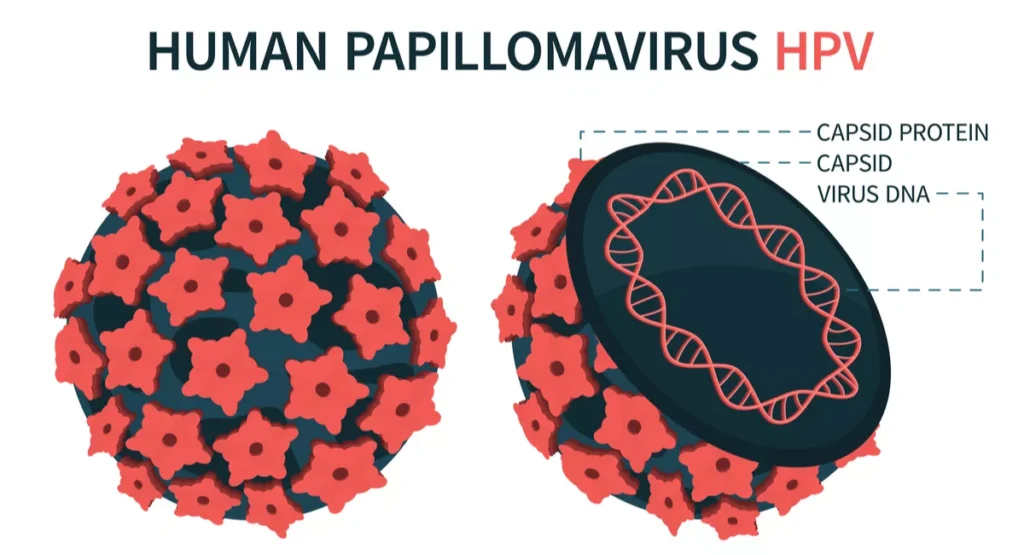

Another method of preventing cancer of the cervix is

To vaccinate all boys and girl around the age of 12 year, before they becoming sexually active- Yes you guessed right, most cervical cancers are sexually transmitted by a virus called the HPV virus, and vaccines against these viruses can prevent cervical cancer. More details available on this site on the health education leaflet-‘What is a PAP smear test’